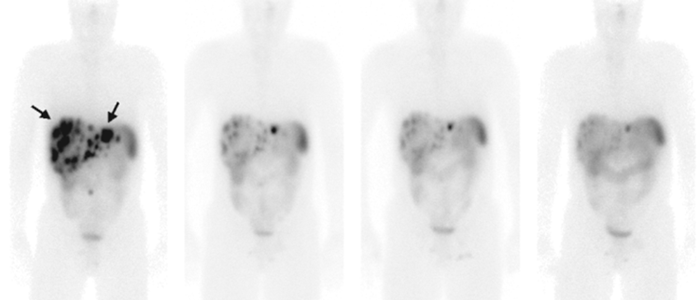

PRRT is de afkorting van Peptide Receptor Radionuclide Therapie. Deze therapie wordt gebruikt bij patiënten met NET en andere zeldzame vormen van kanker. Door het toedienen van het radioactief eiwit lutetium-DOTATATE bij de patiënt kunnen we tumoren met precisie behandelen. Dankzij deze behandeling verbetert in de meeste gevallen de kwaliteit van leven.

Naast de uitvoering van behandelingen worden er in het Erasmus MC ook nieuwe radioactieve therapieën ontwikkeld. Zo is hier de behandeling met peptide receptor radionuclide therapie (PRRT) voor neuro-endocrine tumoren ontwikkeld. Wereldwijd hebben wij hier de meeste patiënten mee behandeld.

Ons team heeft jarenlange ervaring met het geven en ontwikkelen van de verschillende nucleaire therapieën. Zo is in 1992 Peptide Receptor Radionuclide therapie ontwikkeld op onze afdeling, en hebben we sindsdien al meer dan 2500 patiënten behandeld met deze therapie.